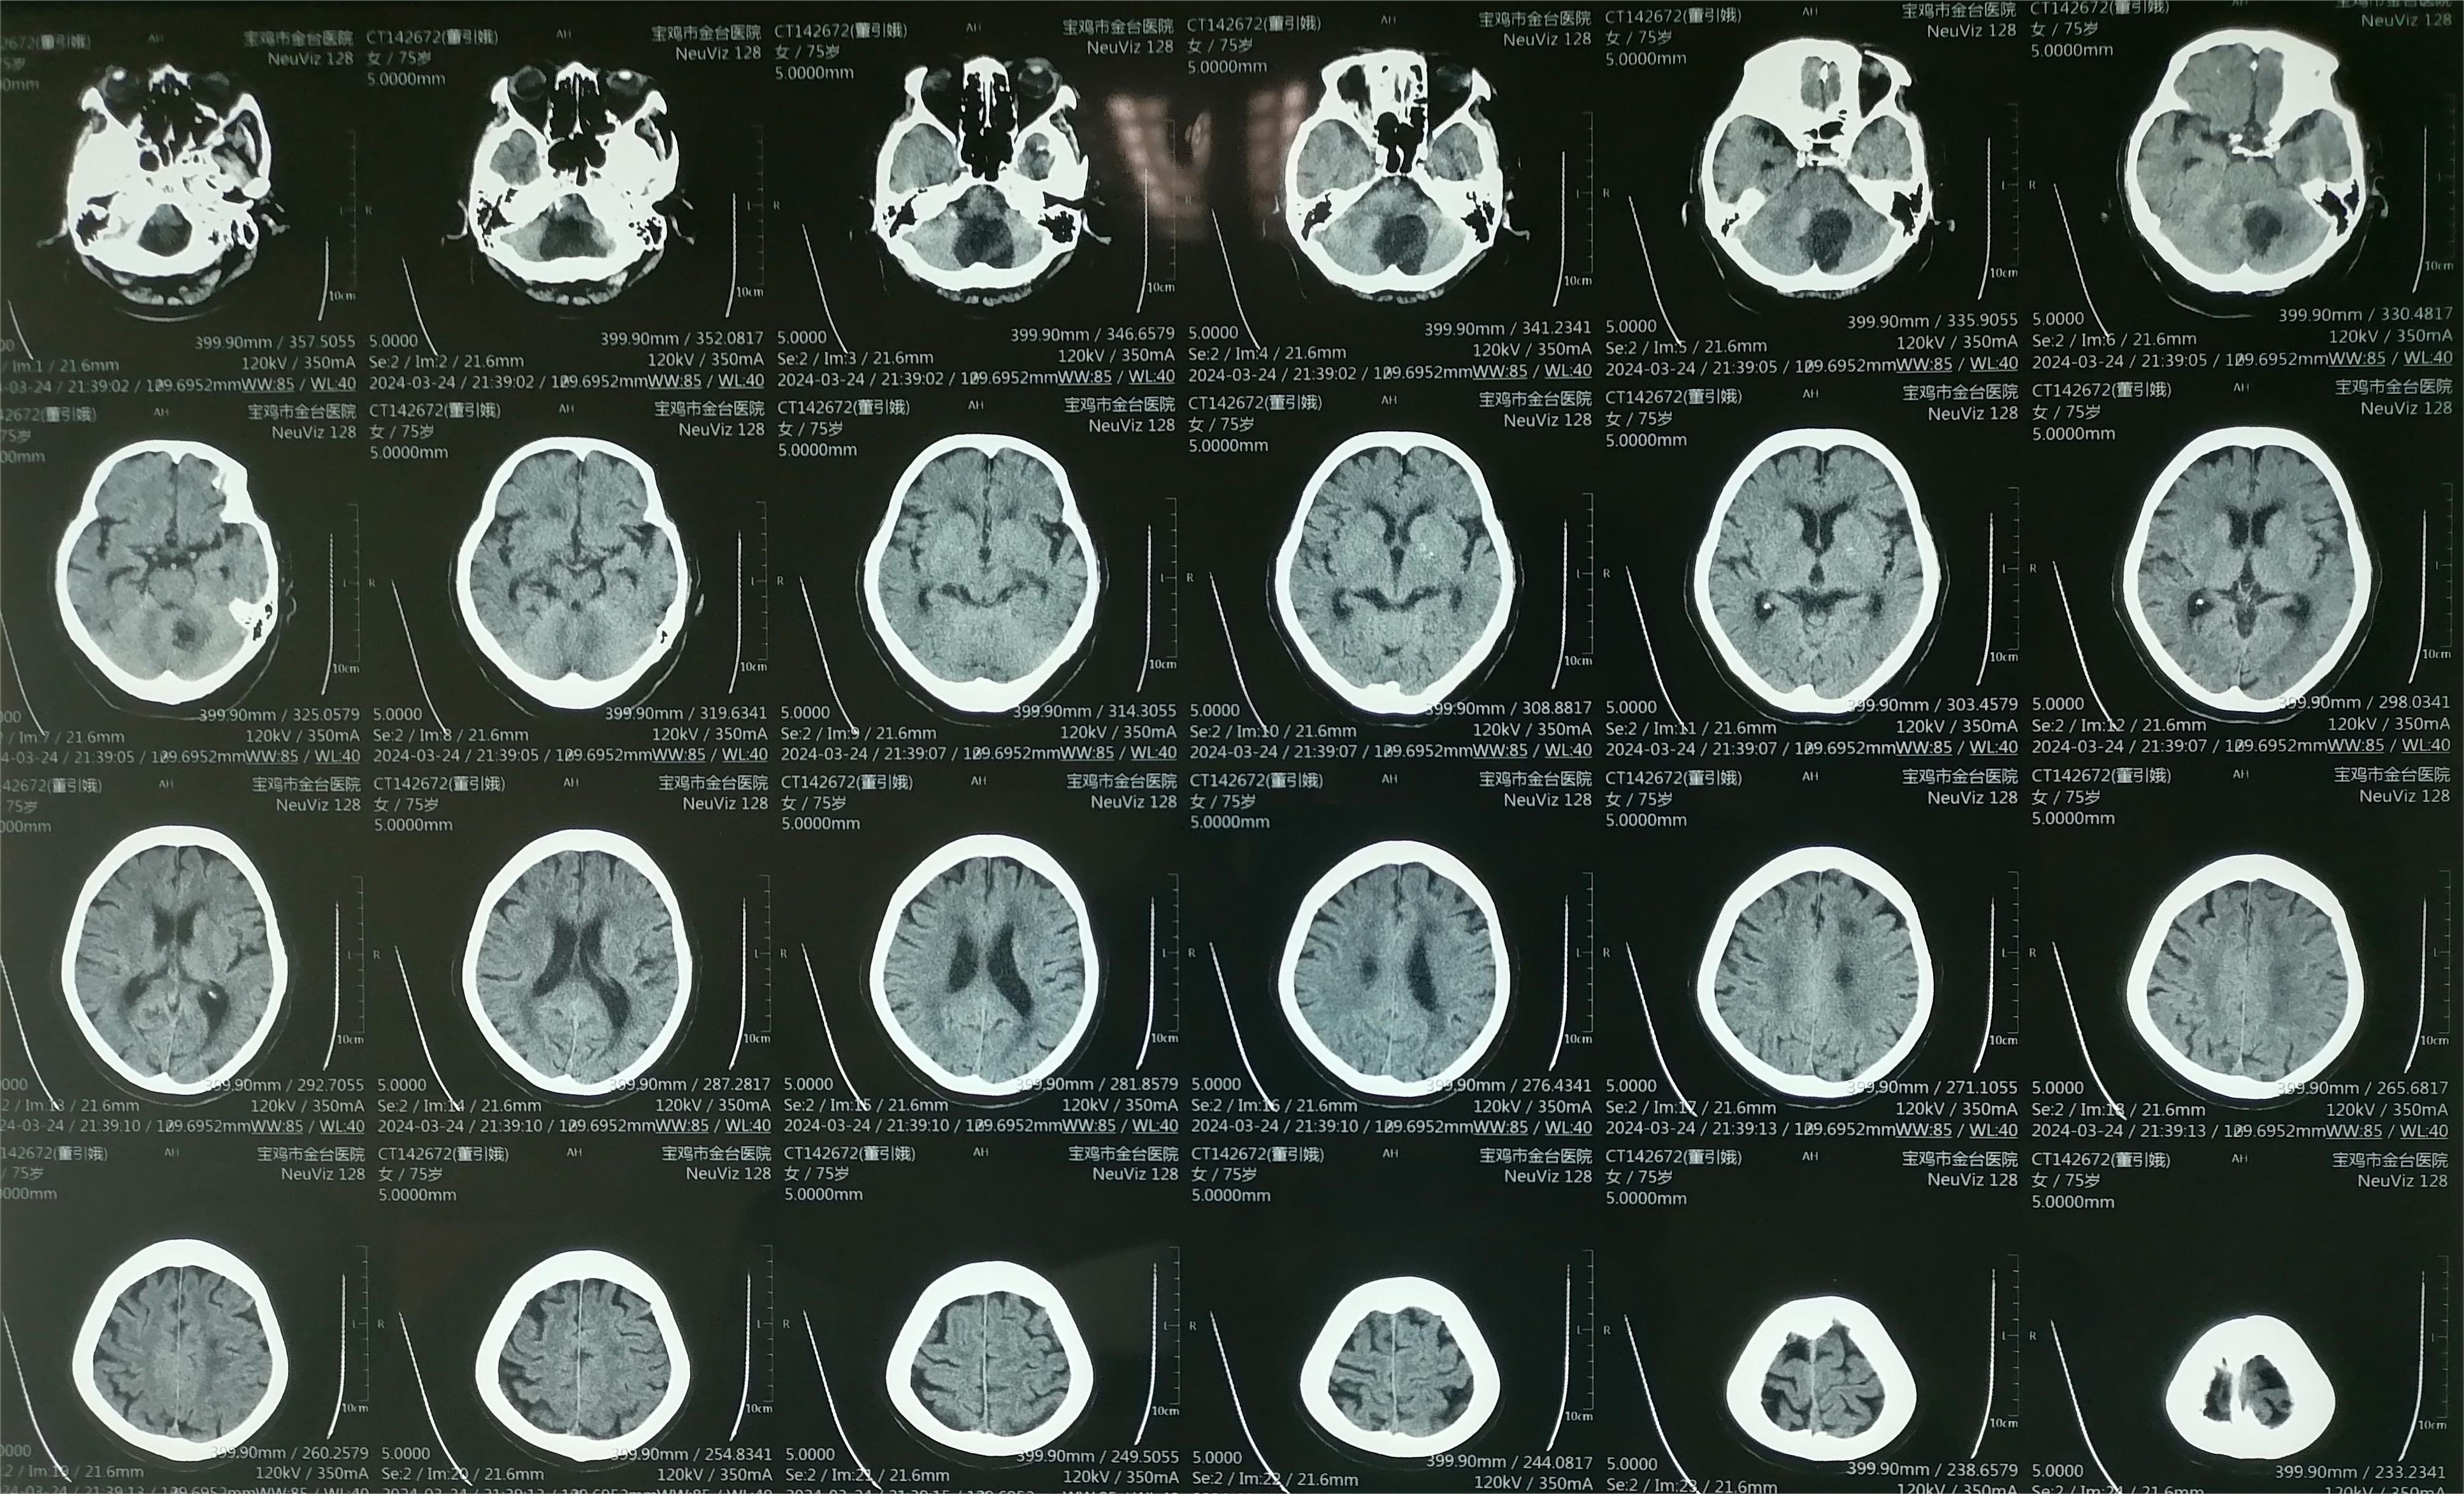

初步诊断:枕大孔区占位性病变 血管母细胞瘤

术前资料